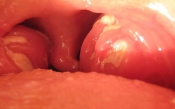

Viêm tai giữa hay nhiễm trùng tai giữa là tình trạng viêm và xuất hiện mủ ở vùng tai giữa.

Viêm tai giữa cấp tính là bệnh rất hay gặp ở trẻ em. Nguyên nhân chủ yếu do bệnh ở mũi họng. Nếu được điều trị sớm và đúng cách, bệnh sẽ khỏi và không có biến chứng. Bệnh thường diễn biến nhanh và kèm với triệu chứng đau nhói trong tai, ù tai tiếng trầm, nghe kém nhẹ kiểu dẫn truyền, khám thấy sưng nề và đỏ trong tai. Các triệu chứng trên là do quá trình viêm gây xuất tiết chất dịch lỏng trong tai giữa.

Viêm tai giữa mạn tính gặp ở mọi lứa tuổi. Bệnh chuyển thành mạn tính khi thời gian chảy mủ tai trên 03 tháng. Tình trạng viêm mạn tính gây ảnh hưởng nhiều đến sức nghe (điếc dẫn truyền), ngoài ra còn gây các biến chứng nguy hiểm như viêm màng não, viêm não, viêm tai xương chũm,…